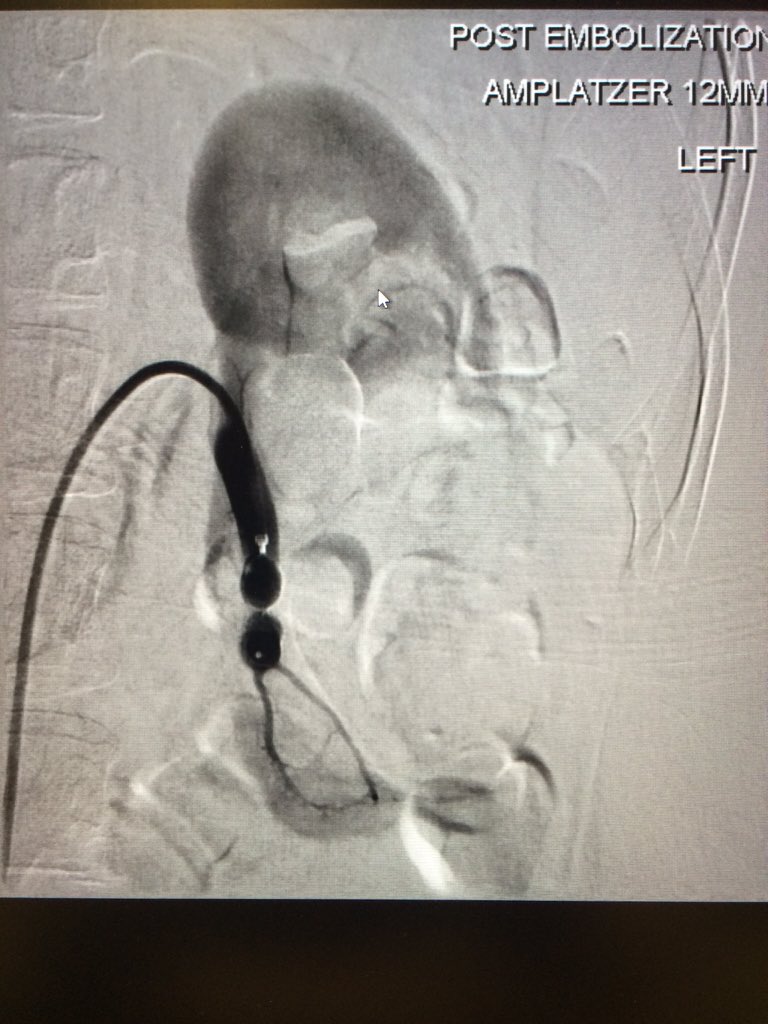

Renal AVM causing a varicocele and Dyspnea- embo X 2 1. AVM-AVP &coils 2. varicocele- STS&AVP -dyspnea resolved on the table #irad SIR RFS

Renal AVM causing a varicocele and Dyspnea- embo X 2

1. AVM-AVP &coils

2. varicocele- STS&AVP

-dyspnea resolved on the table #irad <a href="/SIRRFS/">SIR RFS</a>